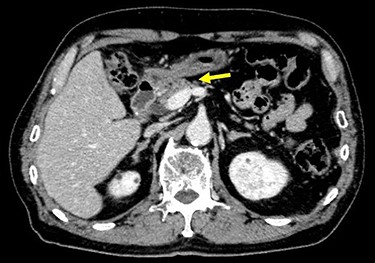

Chest and abdominal computed tomography (CT) showed no distant metastasis, but the tumor of the antrum was clearly visualized and was located close to the pancreatic head (Fig. 1). EGD revealed a large ulcerated lesion at the greater curvature of the antrum (Fig. 2). Hematoxylin and eosin staining of the biopsy specimen of the tumor confirmed a well-differentiated adenocarcinoma (tub1, tub2) (Fig. 3). The assessment of the HER2 expression by immunohistochemistry revealed the overexpression of HER2 (3+) in the biopsy tissue of the gastric tumor (Fig. 4).

Abdominal CT showed the tumor at the gastric antrum visualized as a thickened wall, suggestive of direct invasion to the pancreatic head (arrow).